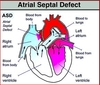

Atrial Septal Defect

-Most common type is ostium secundum (90% of cases)

-Ostium primum type is associated with Down Syndrome

-Results in L –> R shunt, split S2 on auscultation due to increased blood in right heart delays closure of pulmonary valve

-Paradoxical emboli can occur (instead of going to lung to cause PE, go to left side of circulation, end up going to brain or other circulation places)

-Distinct from patent foramen ovale in that septa are missing tissue rather than unfused.